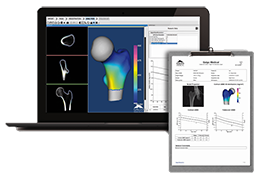

ANYTHINK 经导管主动脉瓣膜置换术分析系统

| 生产厂家: | 北京思创贯宇科技开发有限公司 |